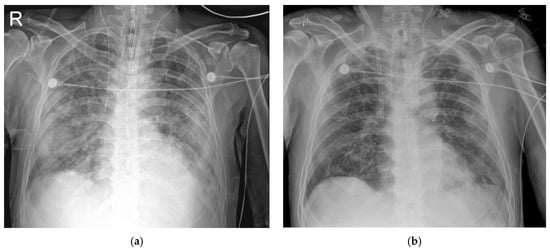

2.1. Case 1

2.2. Case 2